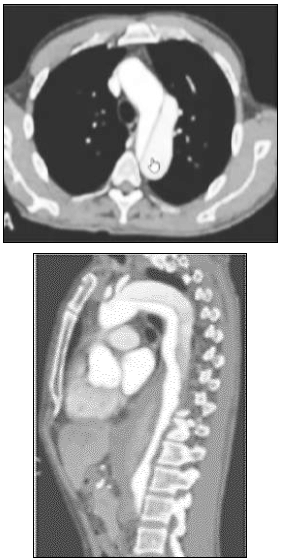

“Homem, 34 anos, refere dor torácica lancinante de início há doze horas; dá entrada no pronto-socorro. À entrada, encontrava- -se com a PA: 180 x 60 mmHg e FC: 105. Diante da suspeita diagnóstica, foi realizado o seguinte exame:”

Após o manejo inicial, o paciente foi submetido ao procedimento cirúrgico com sucesso. Em reavaliação ambulatorial, realizou-se nova angiotomografia de tórax que detectou a presença de endoleak decorrente da porosidade do enxerto. Qual a classificação desse tipo de endoleak?